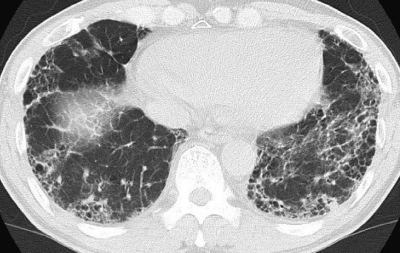

59歳の男性。労作時の呼吸困難を主訴に来院した。3年前から労作時の呼吸困難があったがそのままにしていた。健診で胸部の異常陰影を指摘されたため、心配になり受診した。

身長 172 cm、体重 70 kg。体温 36.3 ℃。脈拍 80/分、整。血圧 128/84 mmHg。呼吸数 18/分。SpO2 95 %(room air)。心音に異常を認めない。呼吸音は正常だが、両側の背部に fine crackles を聴取する。胸部エックス線写真と胸部CTとを示す。